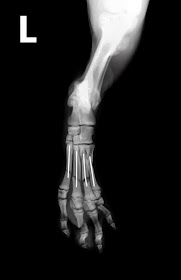

Como ejemplo, comentaré el caso de una paciente,

hembra, de raza mastín español, de seis años y 65 kg de peso que ha empezado a

cojear de su extremidad anterior izquierda, y presenta una tumefacción en radio

distal, cerca del carpo.

Al realizar el correspondiente estudio radiográfico

se obtiene la siguiente imagen:

Esta imagen nos muestra un proceso osteolítico y proliferativo, de origen tumoral, en radio

distal de un paciente de talla grande, que afecta a un solo hueso y no

atraviesa la articulación. Es prácticamente la definición de osteosarcoma, aunque debe hacerse una biopsia para confirmarlo, (podría confundirse con una osteomielitis, principalmente fúngica, aunque afecta a un sólo hueso y no cruza la articulación) pero en la mayoría de los casos la

imagen tiene valor diagnóstico.